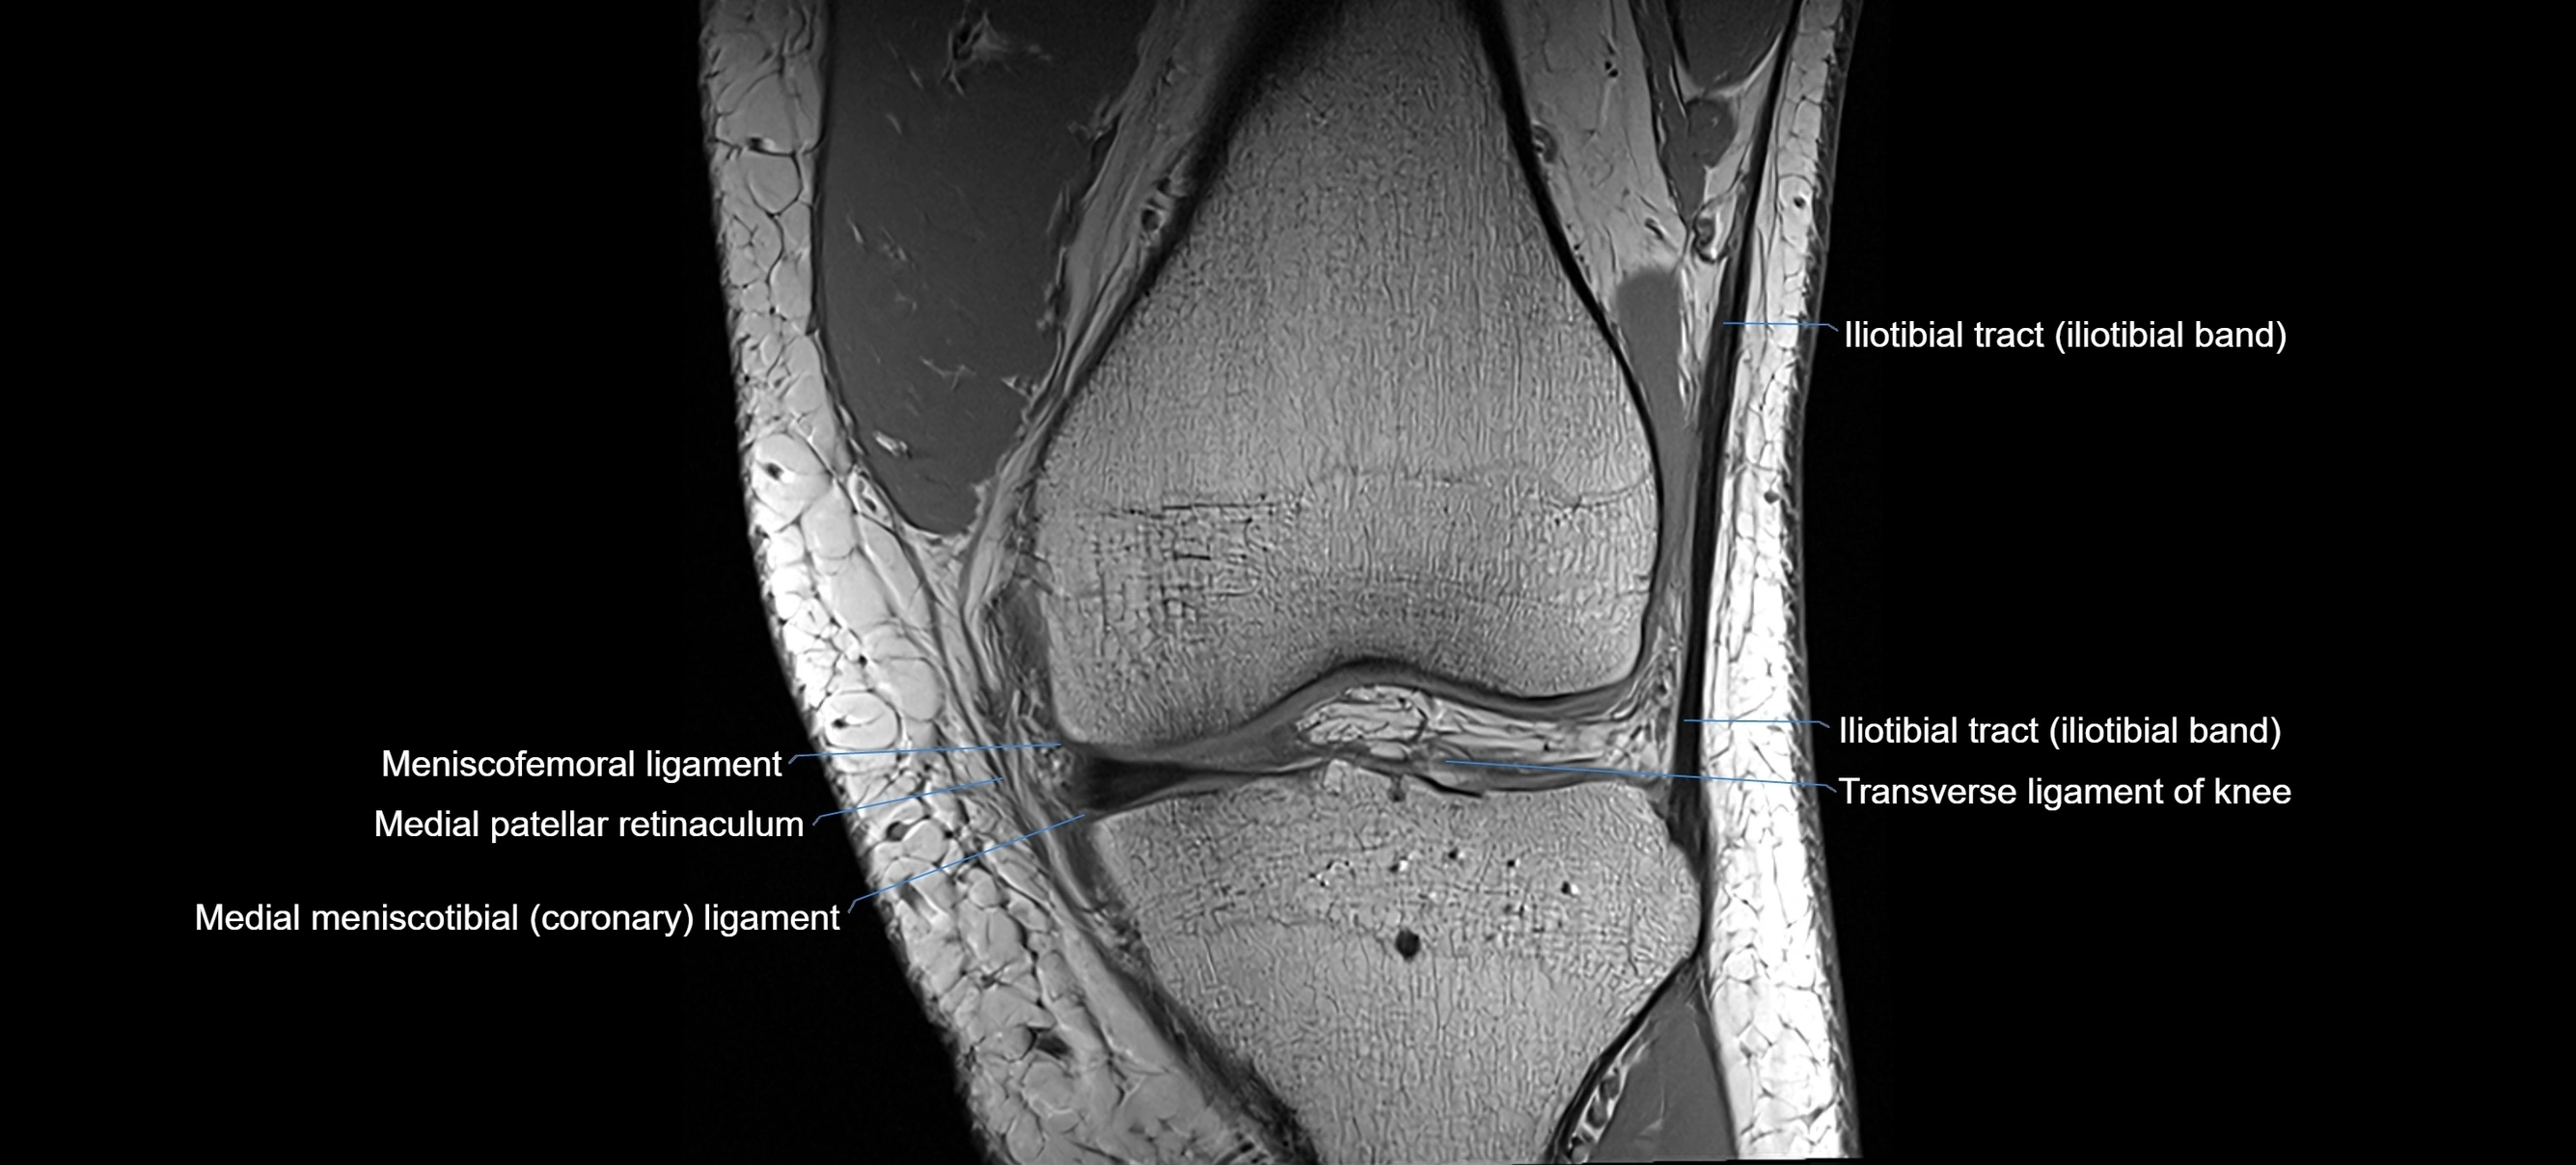

MRI images

image